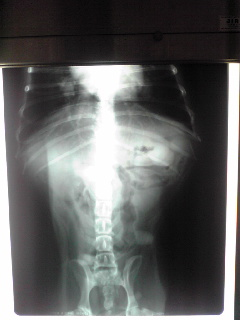

恐る恐るレントゲンを撮ってみると、お腹ペチャンコになってて・・腫瘍は全く写って来ません。。。

なんと消えていました。(*_*)

一年前は、胸に溜まっていた胸水も無くなり、心臓もはっきり写っています。